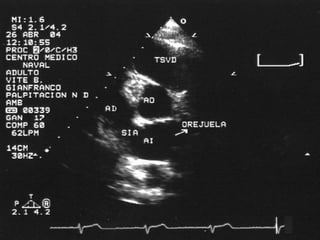

• A nivel de la válvula aortica se puede

observar: Aorta, AI, AD, VD, Válvula

aórtica, con sus tres cúspides (derecha ,

izquierda y no coronariana), válvula

pulmonar, válvula tricuspidea, septum IA,

tronco de la arteria coronaria izquierda

• Permite identificar también el apéndice de

la aurícula izquierda